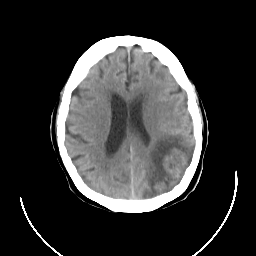

CT Study #3 -- Slice #18

[Home][Help][Clinical][Tour 1] Slice 18